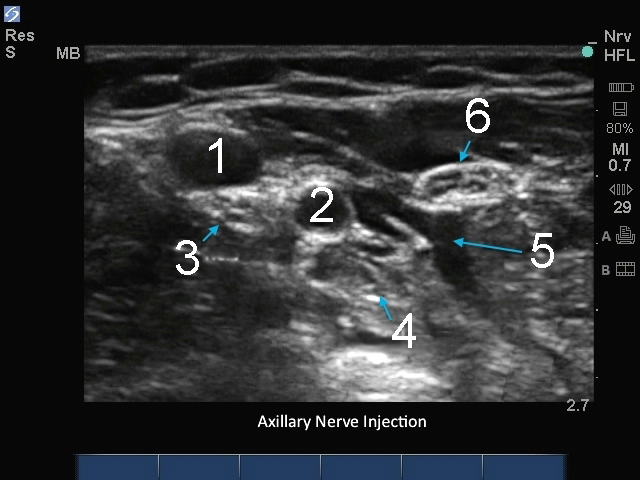

1. Vein

2. Artery

3. Median Nerve

4. Radial Nerve

5. Local Anesthetic

6. Ulnar Nerve